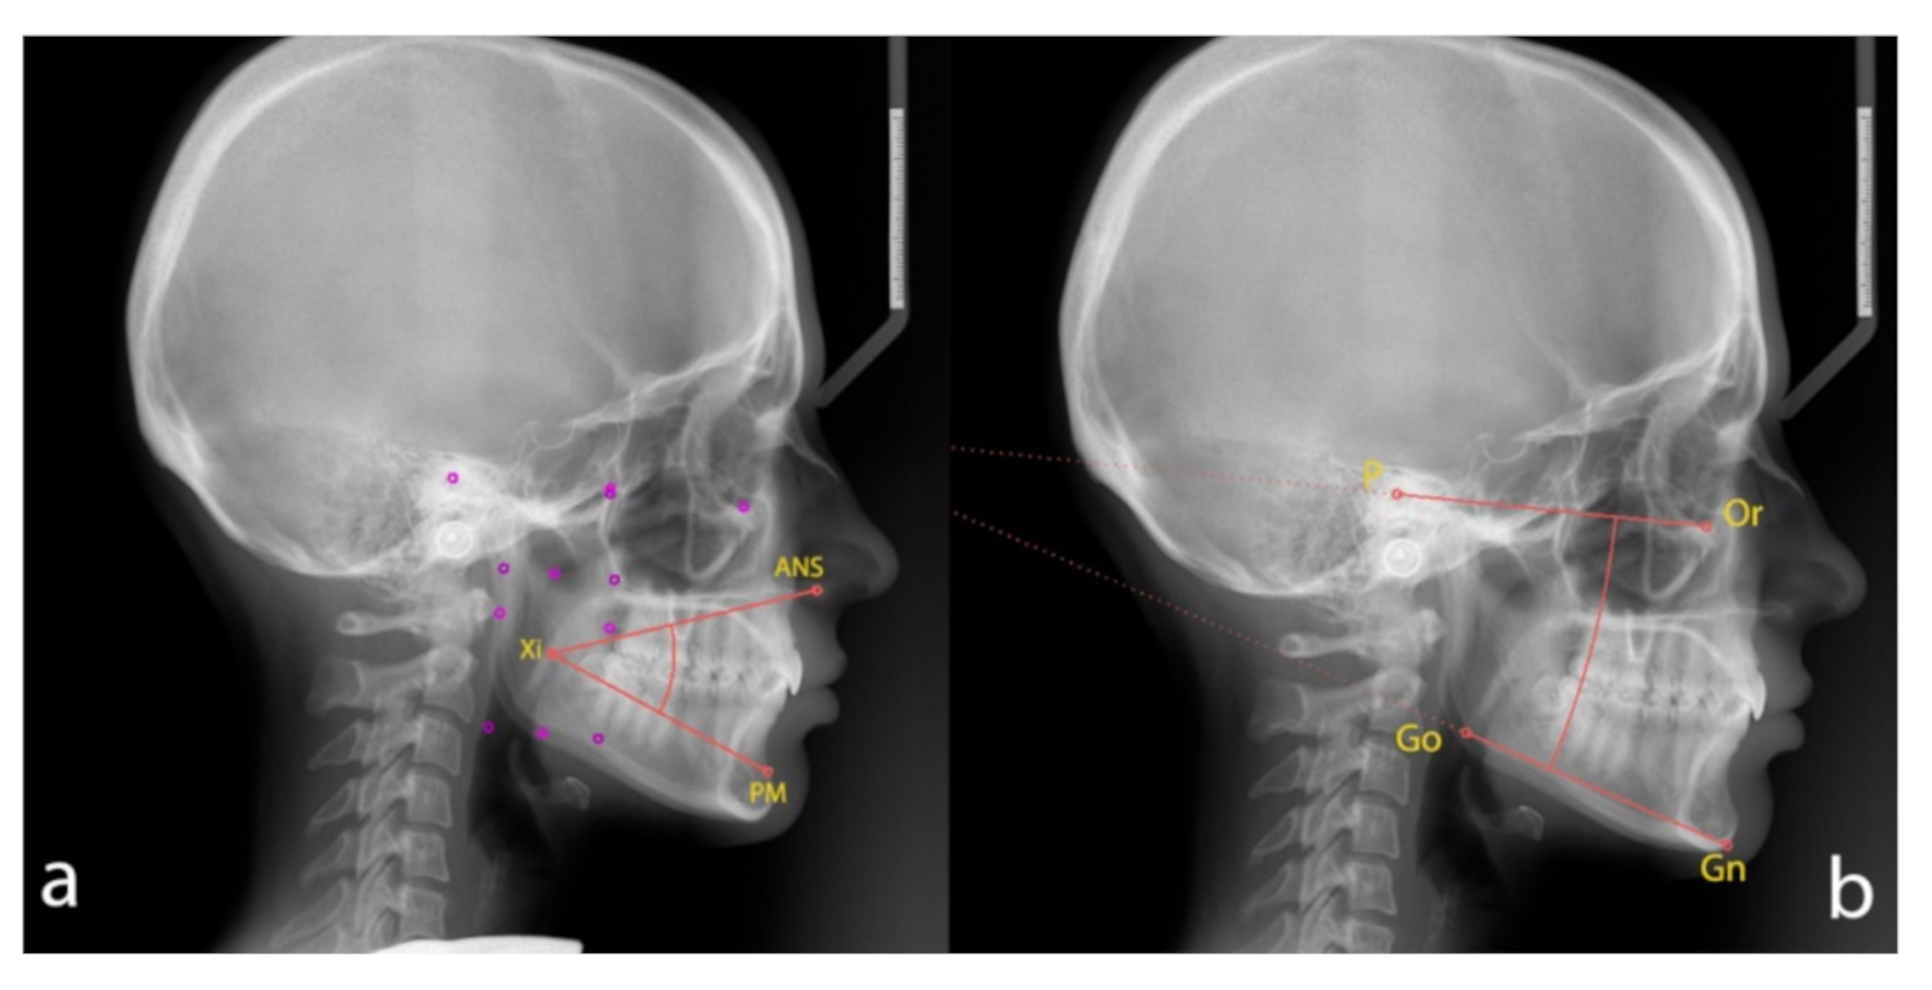

- The lower facial height angle [LFHˆ], between [ANS], [Xi] point and [PM];

- The angle [MLˆFH], between mandibular plane (the plane tangent to the lower edge of the mandibular body, [Gn] and [Go]) and Frankfurt plane ([P] and [Or]).